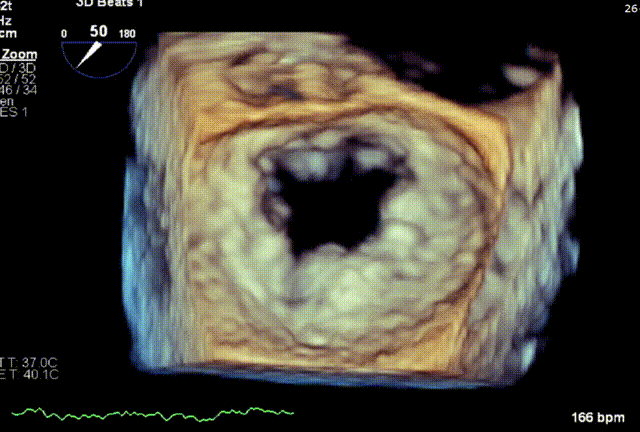

术前3D VIEW